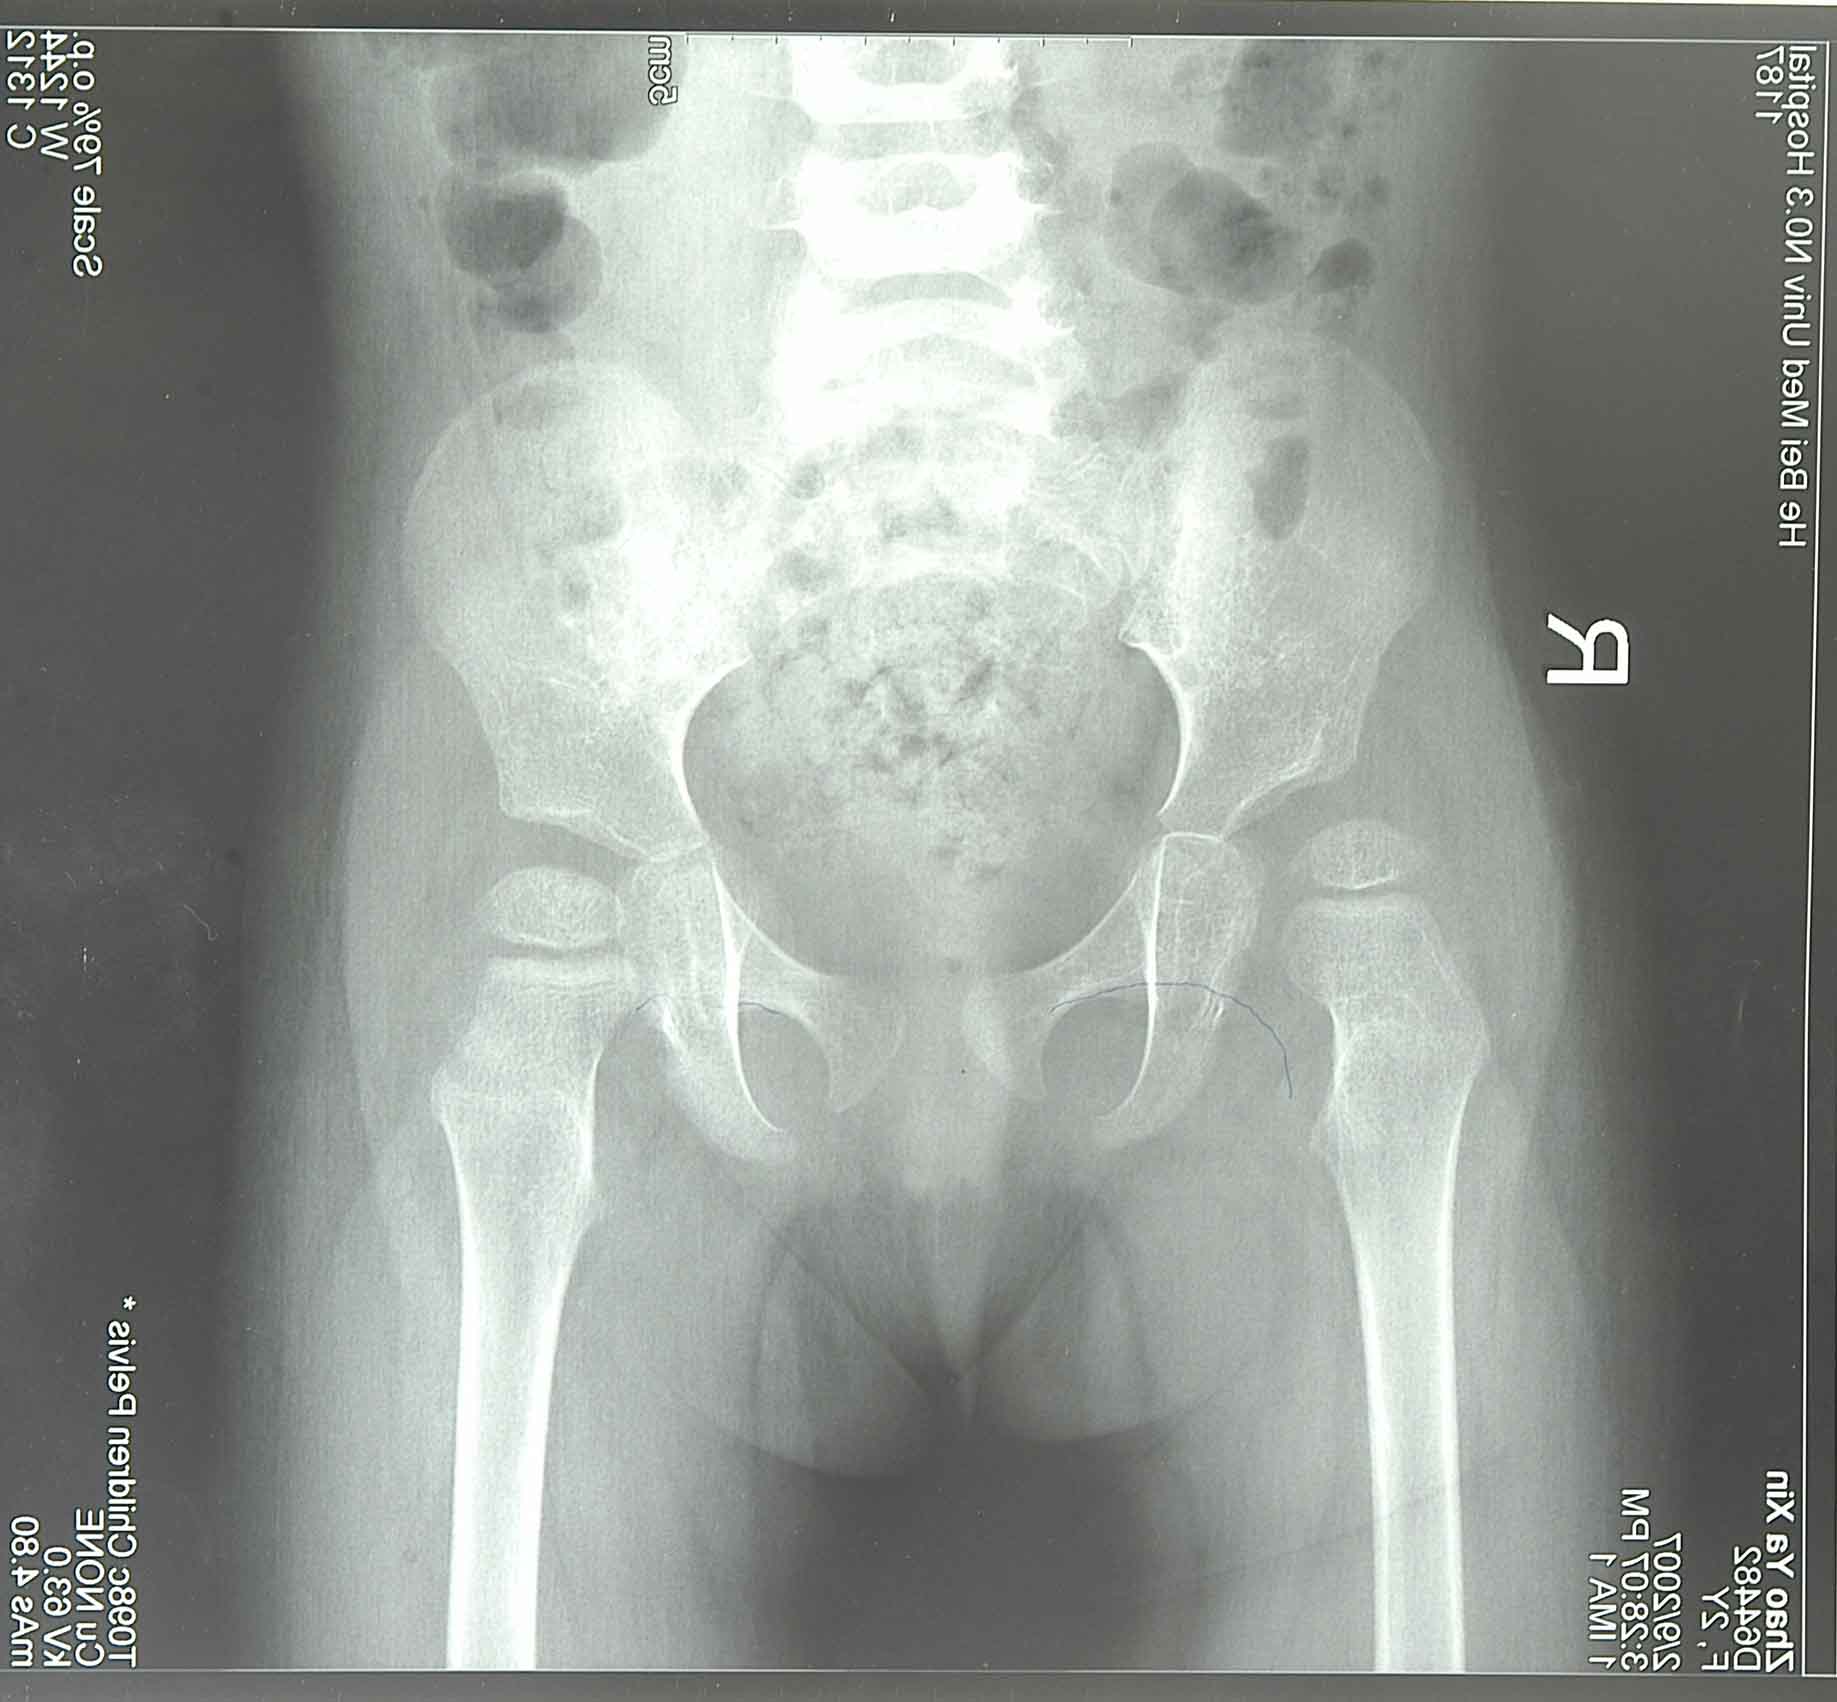

女孩,1岁3个月发现双侧脱位,经过2次石膏1次支架,后又做了1次石膏复位,现在宝宝2岁4个月复查见片子。请求各位专家能给予一些诚恳的意见,接下来我们该采取怎么的治疗方式。不胜感激!

从片子上看,治疗不是很乐观,特别是右侧,脱位还是明显啊。

先保守治疗,后考虑手术,手术包括截骨矫形和韧带松解。从片子上看右侧髋臼较浅,股骨头向外下脱位,骨质轻度疏松,骨骺较左侧发育小,已经治疗1年1月,再保守治疗半年多情况吧,祝你女儿早日康复。